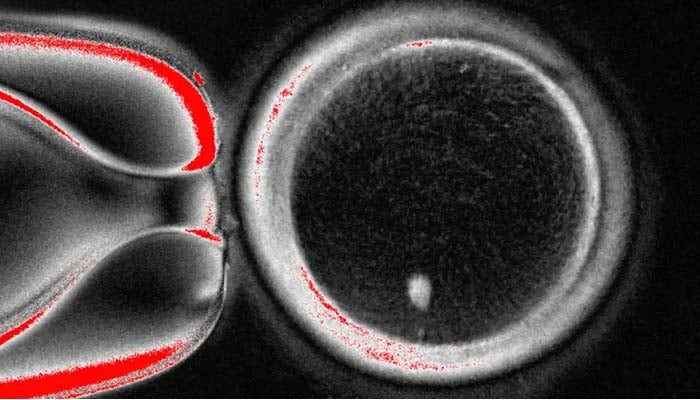

Nearly 9% of the resulting embryos survived for six days, reaching the blastocyst stage, an early phase of development.